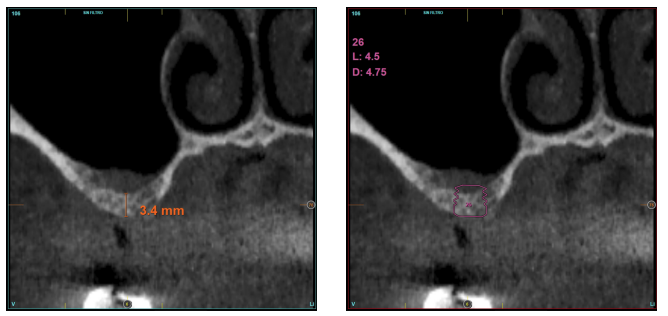

En las Figuras 2- 19 se muestra uno de los casos incluidos en el estudio.

la oseointegración del implante 6 meses después de la cirugía. Se observa una ganancia ósea de 4 mm.

en altura de 3,4 mm, siendo más uniforme en esta ocasión en toda la zona de la cresta. Se planifica un implante de 4,5 mm de longitud y

4,75 mm de diámetro.

implante y el volumen óseo ganado y conservado tras la función de los implantes.